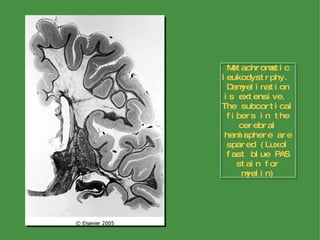

Metachromatic Leukodystrophy This disorder is transmitted in an autosomal-recessive pattern and results from a deficiency of the lysosomal enzyme  arysulfatase A Enzyme deficiency leads to an accumulation of the sulfatides, especially cerebroside sulfate The gene for arylsulfatase A has been localized to chromosome 22q

Metachromatic Leukodystrophy Clinical subtypes of the disorder include a late infantile form (the most common), a juvenile form, and an adult form The two forms with childhood onset often present with motor symptoms and progress gradually, leading to death in 5 to 10 years In the adult form, psychiatric or cognitive symptoms are the usual initial complaint, with motor symptoms coming later, and the disease has a slower course

Metachromatic Leukodystrophy The most striking histologic finding is demyelination with resulting gliosis Macrophages with vacuolated cytoplasm are scattered throughout the white matter The membrane-bound vacuoles contain complex crystalloid structures composed of sulfatides When bound to certain dyes such as toludine blue, sulfatides shift the absorbance spectrum of the dye, a property called  metachromasia The detection of metachromatic material in the urine is also a sensitive method of establishing the diagnosis

Metachromatic leukodystrphy.  Demyelination is extensive.  The subcortical fibers in the cerebral hemisphere are spared (Luxol fast blue PAS stain for myelin)